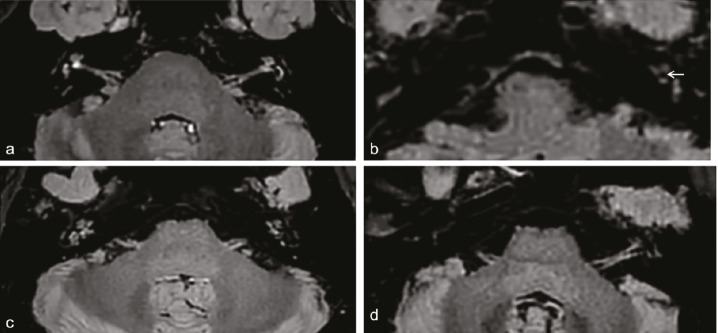

Purpose: To evaluate the diagnostic performance of delayed post-gadolinium enhancement magnetic resonance imaging (DEMRI) in diagnosing Menière’s disease (MD) and to establish an effective MRI-based diagnostic model.

Methods: This retrospective multicenter study assessed DEMRI descriptors in patients presenting with Ménièriform symptoms who were examined consecutively between May 2022 and May 2024. A total of 162 ears (95 with MD, 67 controls) were included. Each ear was randomly assigned to either a training set (n = 98) or a validation set (n = 64). In the training cohort, diagnostic models for MD were developed using logistic regression. The area under the curve (AUC) was used to evaluate the diagnostic performance of the different models. The Delong test was applied to compare AUC estimates between models.

Results: The proposed DEMRI diagnostic model demonstrated strong diagnostic performance in both the training cohort (AUC: 0.907) and the validation cohort (AUC: 0.887), outperforming the clinical diagnostic model (P = 0.01231; 95% confidence interval: 0.033–0.269) in the validation cohort. The AUC of the DEMRI model was also higher than that of the combined DEMRI-clinical model (AUC: 0.796), although the difference was not statistically significant (P = 0.054). In the training set, the sensitivity and specificity of the DEMRI model were 78.9% and 88.5%, respectively.

Conclusion: A diagnostic model based on DEMRI features for MD is more effective than one based solely on clinical variables. DEMRI should, therefore, be recommended when MD is suspected, given its significant diagnostic potential.

Abstract Image